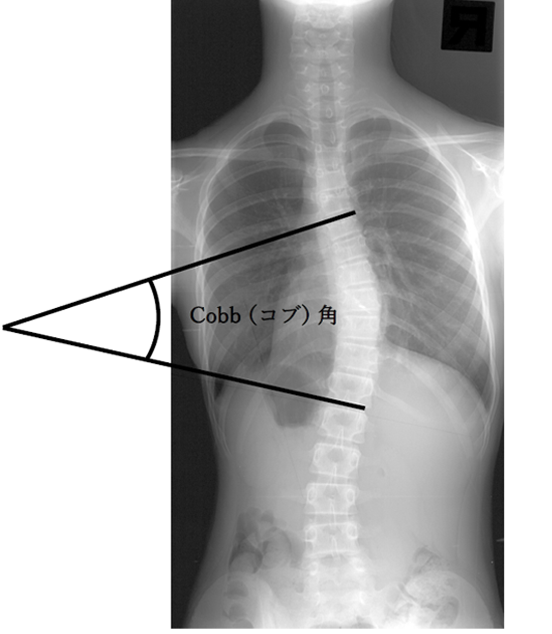

側弯の診断とコブ角

側弯症は、レントゲン検査によって診断され、背骨の弯曲の程度は図のように、「コブ角」という指標で表されます。「コブ角」とは、脊柱の上下で最も曲がりの強い椎体から直線を伸ばし、その 2本の直線の交差する角度のことを示します。

この「コブ角」が 10°以上の場合、「側弯症」と診断されます。